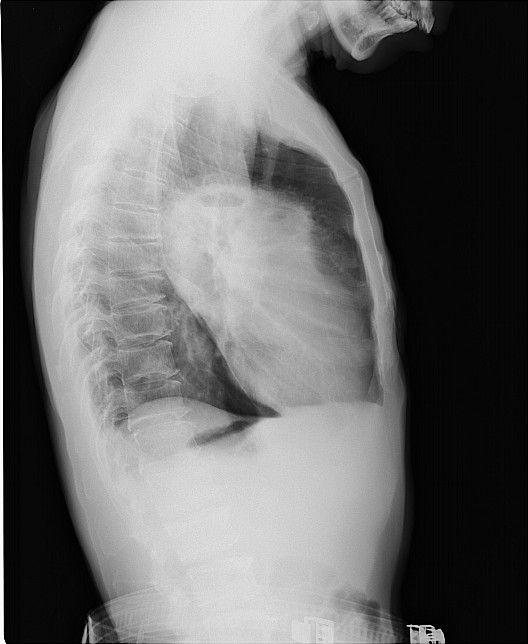

标题: X3612:男,48岁,咳嗽气逼月余 [打印本页]

标题: X3612:男,48岁,咳嗽气逼月余

实性包块,上有小液平,如无脓肿症状,考虑肺癌

肺脓肿应该是边缘不清楚吧,而这个好象是块状密度增高影,所以我觉得是周围性肺癌引起的空洞.